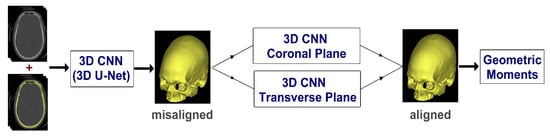

Thus, this study aims to present a 3D technique for automatically calculating the craniofacial symmetry midplane from CT scans using convolutional neural network (CNN) and geometric moments. Figure 1 shows the overview of the proposed method. First, using 3D U-net, the skull is removed from CT images to create a dataset. Then, based on the cephalometric landmarks, the CT image is aligned in the coronal and transverse planes. The image is then duplicated and two datasets of 441 images, per image, of 0.5° resolution is created from −5° to 5°. These sets of images are presented to a 3D rotate invariant CNN. After CNN determines the rotation degree of these images in the coronal and transverse planes, the skull midpoints are calculated using 3D geometric moments. Finally, by joining the midpoints and grades described by the CNN, the midplanes can be constructed.

Figure 1.

Overview of the proposed method. CNN: convolutional neural network.